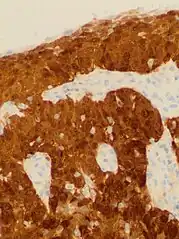

Positive visual inspection with acetic acid of the cervix for CIN-1

Checking cervical cells with the Papanicolaou test (Pap test) for cervical pre-cancer has dramatically reduced the number of cases of, and mortality from, cervical cancer.[24] Liquid-based cytology may reduce the number of inadequate samples.[69][70][71] Pap test screening every three to five years with appropriate follow-up can reduce cervical cancer incidence up to 80%.[72]